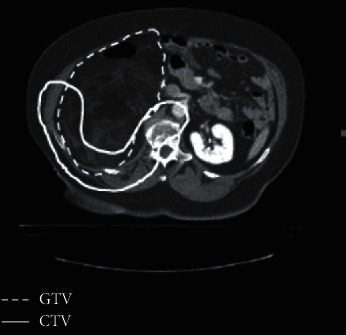

Methods: We performed a comparative study of treatment plans with 3D CPT, IMPT, and IMXT for ten patients with retroperitoneal sarcomas. RT was delivered to 50.4 Gy to the clinical target volume (CTV), the structures considered at risk for microscopic disease.

Results: CTVs ranged from 74 to 357 cc (mean 188 cc). Dose conformity was improved with IMPT, while 3D CPT provided better dose homogeneity. Mean dose to the liver, small bowel, and stomach was reduced with IMPT compared with 3D CPT or IMXT.